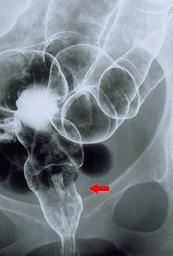

Criteria of Hist.ClassificationMalignant epithelial tumor/Signet-ring cellcarcinoma

LocationLarge intestine(Colon)/Rectum

Technique, MethodX-ray

Macroscopic TypesType 3 Ulcerated type with infiltration/

Size35 - 40

Depth of Tumor Invasionserosa (adventitia)